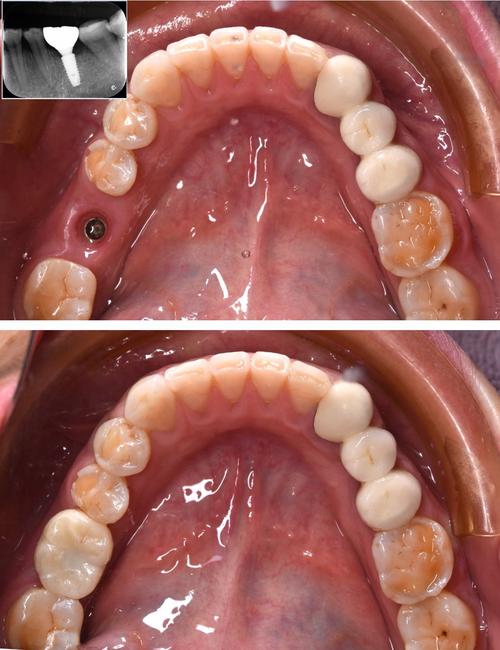

(图片来源网络,侵删)- 原因: 种植部位牙槽骨高度、宽度或厚度不足;骨密度低(如骨质疏松、长期缺牙导致骨吸收);骨结构不良(如存在病变、放疗后骨),医生术前评估不足,或未进行必要的骨增量手术(植骨)。

(图片来源网络,侵删)- 原因: 缝合技术不佳;术后局部创伤(如撞击、频繁漱口);患者体质差;感染。